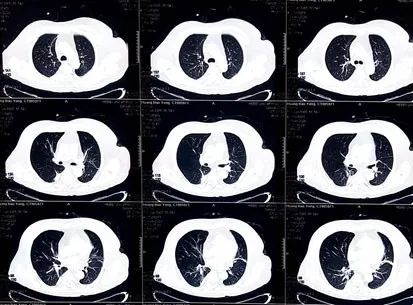

图9. 复查胸部CT(2020-02-11):与2020-02-02扫描比较,双肺病灶有所吸收,双侧胸膜增厚程度减轻。

(5)患者咳少量白痰,双肺散在炎症,复查胸部CT示双肺炎症加重,双侧胸膜新发增厚,白细胞增高,C反应蛋白增高,降钙素原正常。

给予该患者甲泼尼龙琥珀酸钠1 g/d冲击治疗,联合抗生素、保肝、营养神经等治疗,其肌钙蛋白水平迅速下降,三度房室传导阻滞完全恢复,肝肾功能恢复正常,肺炎消退,心肌炎和肌炎的症状逐渐减轻,改为甲泼尼龙口服,出院随访。